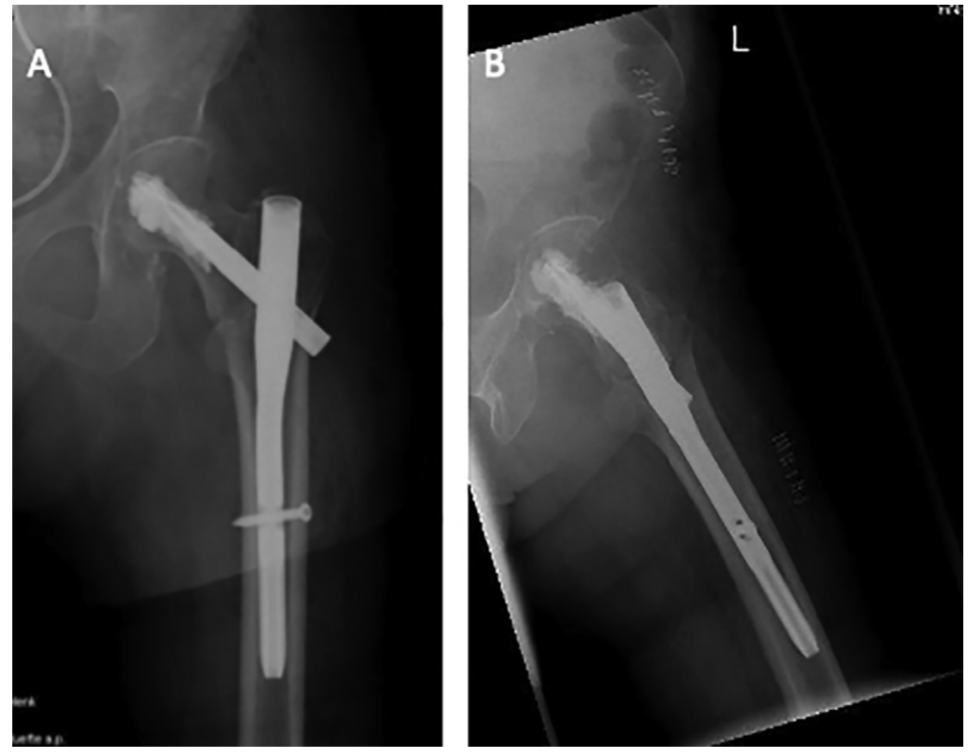

股骨转子间骨折行PFNA内固定,自螺旋刀片注入骨水泥增强。